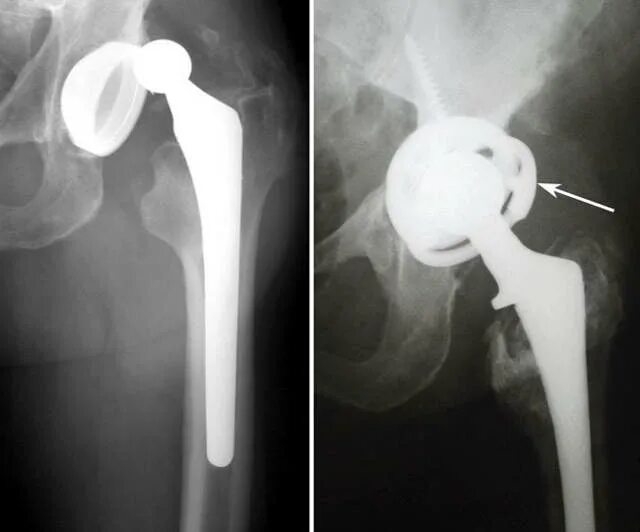

После эндопротезирования 2 суставов прошло